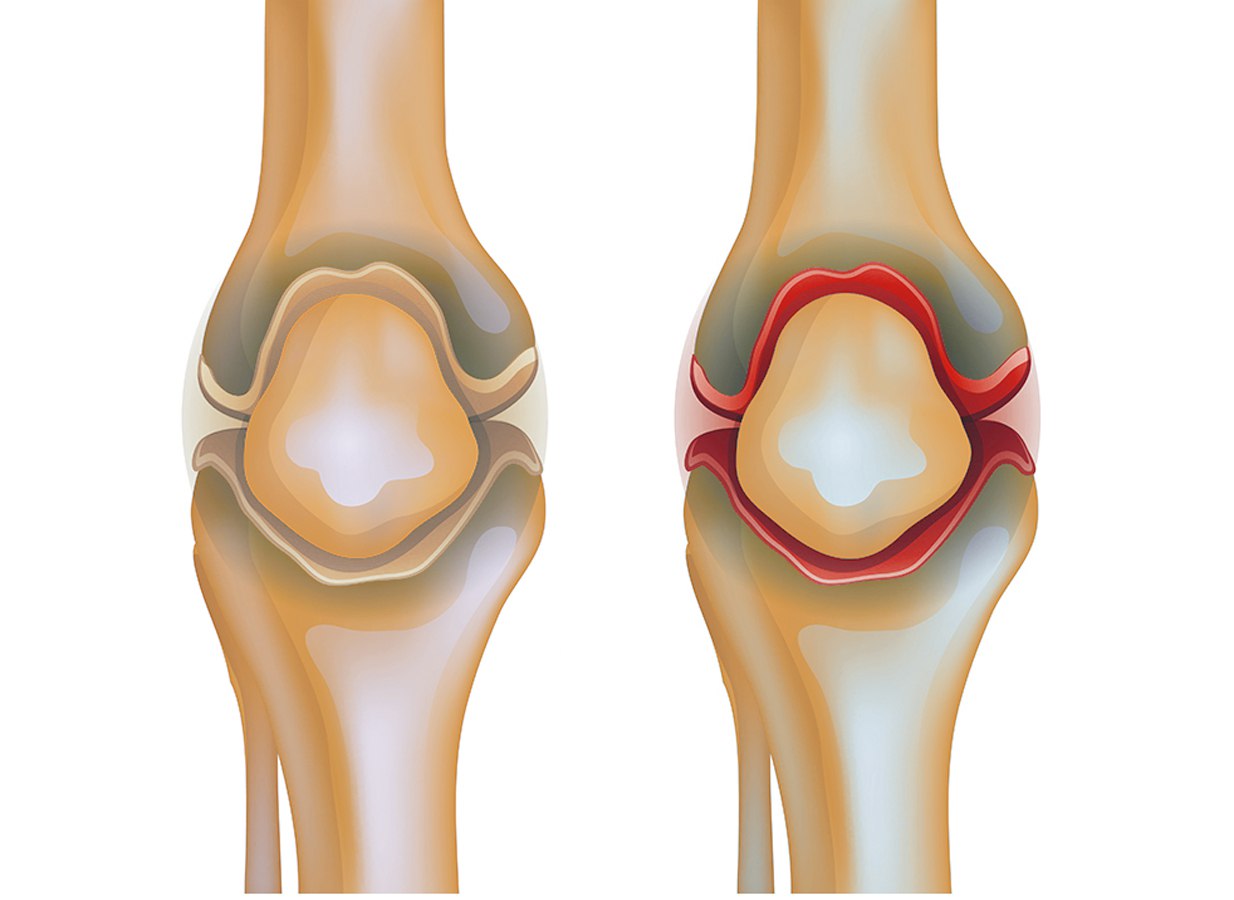

Заболевания и медицинские снимки: Жидкость в коленной чашечке

Раздел: Галерея прозрений